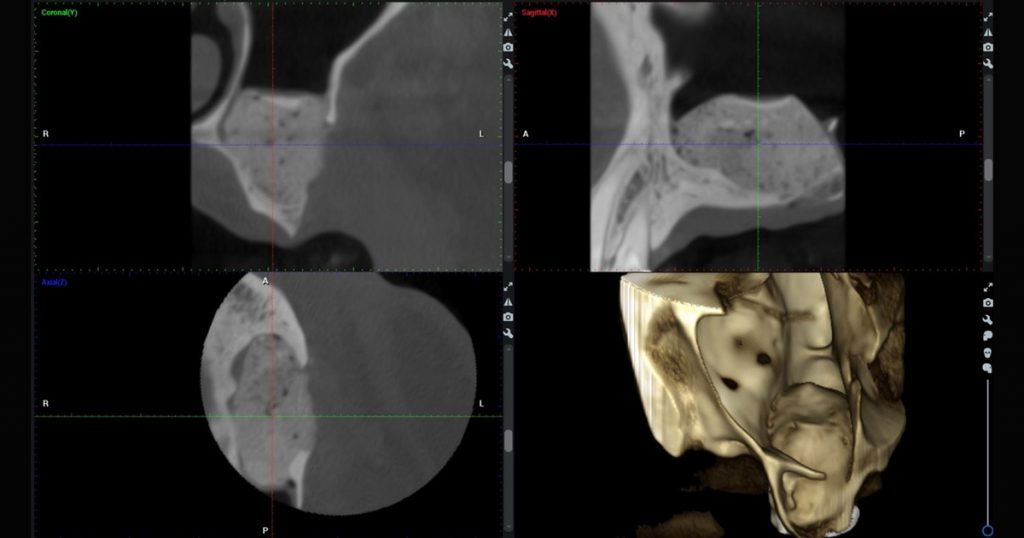

Treatment planning begins with conebeam computed tomography (CBCT) to measure residual bone height (RBH) and evaluate sinus anatomy. A commonly used classification divides cases into three groups:

Residual bone height is not the only factor. Sinus membrane thickness, presence of septa, and access to multiple implant sites also influence technique selection.

- CBCT-based virtual planning of window location and size

- 3D-printed surgical guides enhance accuracy

- Improves consistency and reproducibility